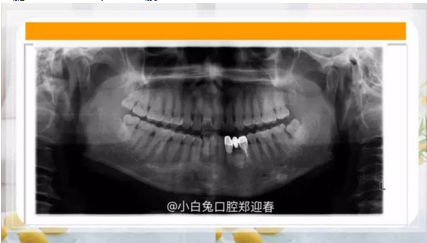

再看看逆襲的尖牙阻生。。。

小泥鰍

16.png

橫位

17.png

18.png

錯(cuò)位

19.png

大尺度異位